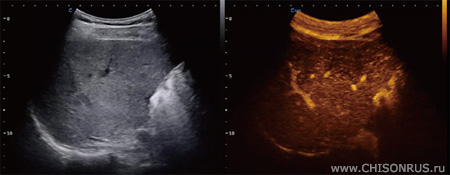

Чаще контраст используется в онкологии для идентификации границ новообразования. При этом обычный В-режим или ЦДК не позволяет получить эти данные. Пример ниже: слева изображение в В-режиме, справа - в режиме конрастирования. Для использования визуализации контраста в аппарате должна быть установлена опция Sono Contrast, а используемый датчик также должен поддерживать этот режим.

Примеры: